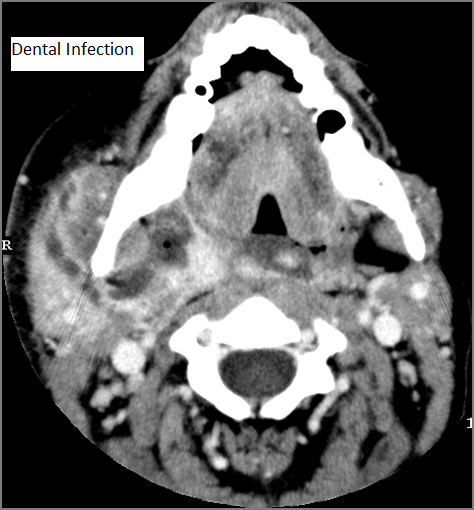

Oral Cavity, Floor of the Mouth, Maxilla and Mandible

There is significant abnormality of these structures that would be an alternate explanation for the patient’s symptoms.

Major Salivary Glands

There is significant abnormality of the parotid, submandibular or sublingual glands that would be an alternate explanation for the patient’s symptoms.